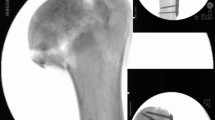

During the preoperative planning, the surgeon was able to interactively set the cutting plane's position and orientation in the virtual humerus. Thereafter, the models were imported into in-house–developed planning software, CASPA (Balgrist CARD AG, Zürich, Switzerland). A humerus-specific cutting guide was used in all elbow specimens, which snugly fitted to the bone geometry (see Fig. 1A). Based on files provided in the stereolithography format, the biocompatible polyamide cutting guides were 3D printed with a 3D printer (Prusa i3 MK3S kit, Prague, Czech Republic). The guides were used to create a standardized, complex plane fracture of the capitellum with posterior comminution (Dubberley IIB). For this purpose, the guide's body was shaped in a way that it could be uniquely placed by using characteristics of the irregular-shaped surfaces of the distal humerus [19, 29] (Fig. 1B). After registering the fracture situation, the guide position was maintained by placing reference K-wires through drill sleeves connected to the guide body of the primary guide and a cutting slit [19] to constrain the saw blade according to the planned osteotomy plane [29]. The posterolateral column fragment was finally split into two separate fragments after the cuts with the guide were performed.

Two parallel 0.8 mm K-wires were placed in an anteroposterior direction into the capitellum perpendicular to the fracture line with about 1 cm distance in between. Screw length was measured with a cannulated depth gauge and partially threaded HCS with a 2.2 mm diameter (Speedtip CCS 2.2 mm, Medartis, Basel, Switzerland) were used. Screw length was chosen just 2 mm shorter than measured, to avoid penetrating the posterior cortex. The cartilage and subchondral bone of the first cortex was predrilled with a cannulated 1.8 mm drill. The self-drilling and self-tapping cannulated HCS screws were gently introduced with a screwdriver into a final position just about 0.5–1 mm below the cartilage level. After placement of two anteroposterior HCS (Speedtip CCS 2.2 mm, Medartis, Basel, Switzerland), additional fracture stabilization was performed using an anterior antiglide plate. Therefore, a 2.0 mm frame plate (Trilock, Medartis, Basel, Switzerland) was adjusted to the specific anatomy of each distal humerus to prevent the proximal dislocation of the capitellum. Care was taken to allow at least 120° of flexion in the radiocapitellar joint. The plate was fixed with three 2 mm bicortical proximal screws, directed in a posterolateral direction to avoid posterior screw impingement in the olecranon fossa. The medial and posteromedial fragments were additionally fixed with two separate 2.8 mm cortical screws placed in a lateromedial direction (Fig. 2A).

A posterolateral distal humerus locking plate (Trilock 2.8 mm, Medartis, Basel, Switzerland) was adjusted to the individual anatomy of the distal humerus. Initial fixation was performed with proximal 2.8 mm cortical screws. Afterwards, the fracture was fixed with three posteroanterior locking screws placed into the subchondral bone of the capitellum through the distal holes of the plate, perpendicular to the fracture line. The adequate length of the screws was chosen to a position 1 to 2 mm below the articular cartilage. The medial and posteromedial fragments were additionally fixed with two separate 2.8 mm cortical screws placed in a lateromedial direction, with the distal screw placed through the extension hole of the plate (Fig. 2B).